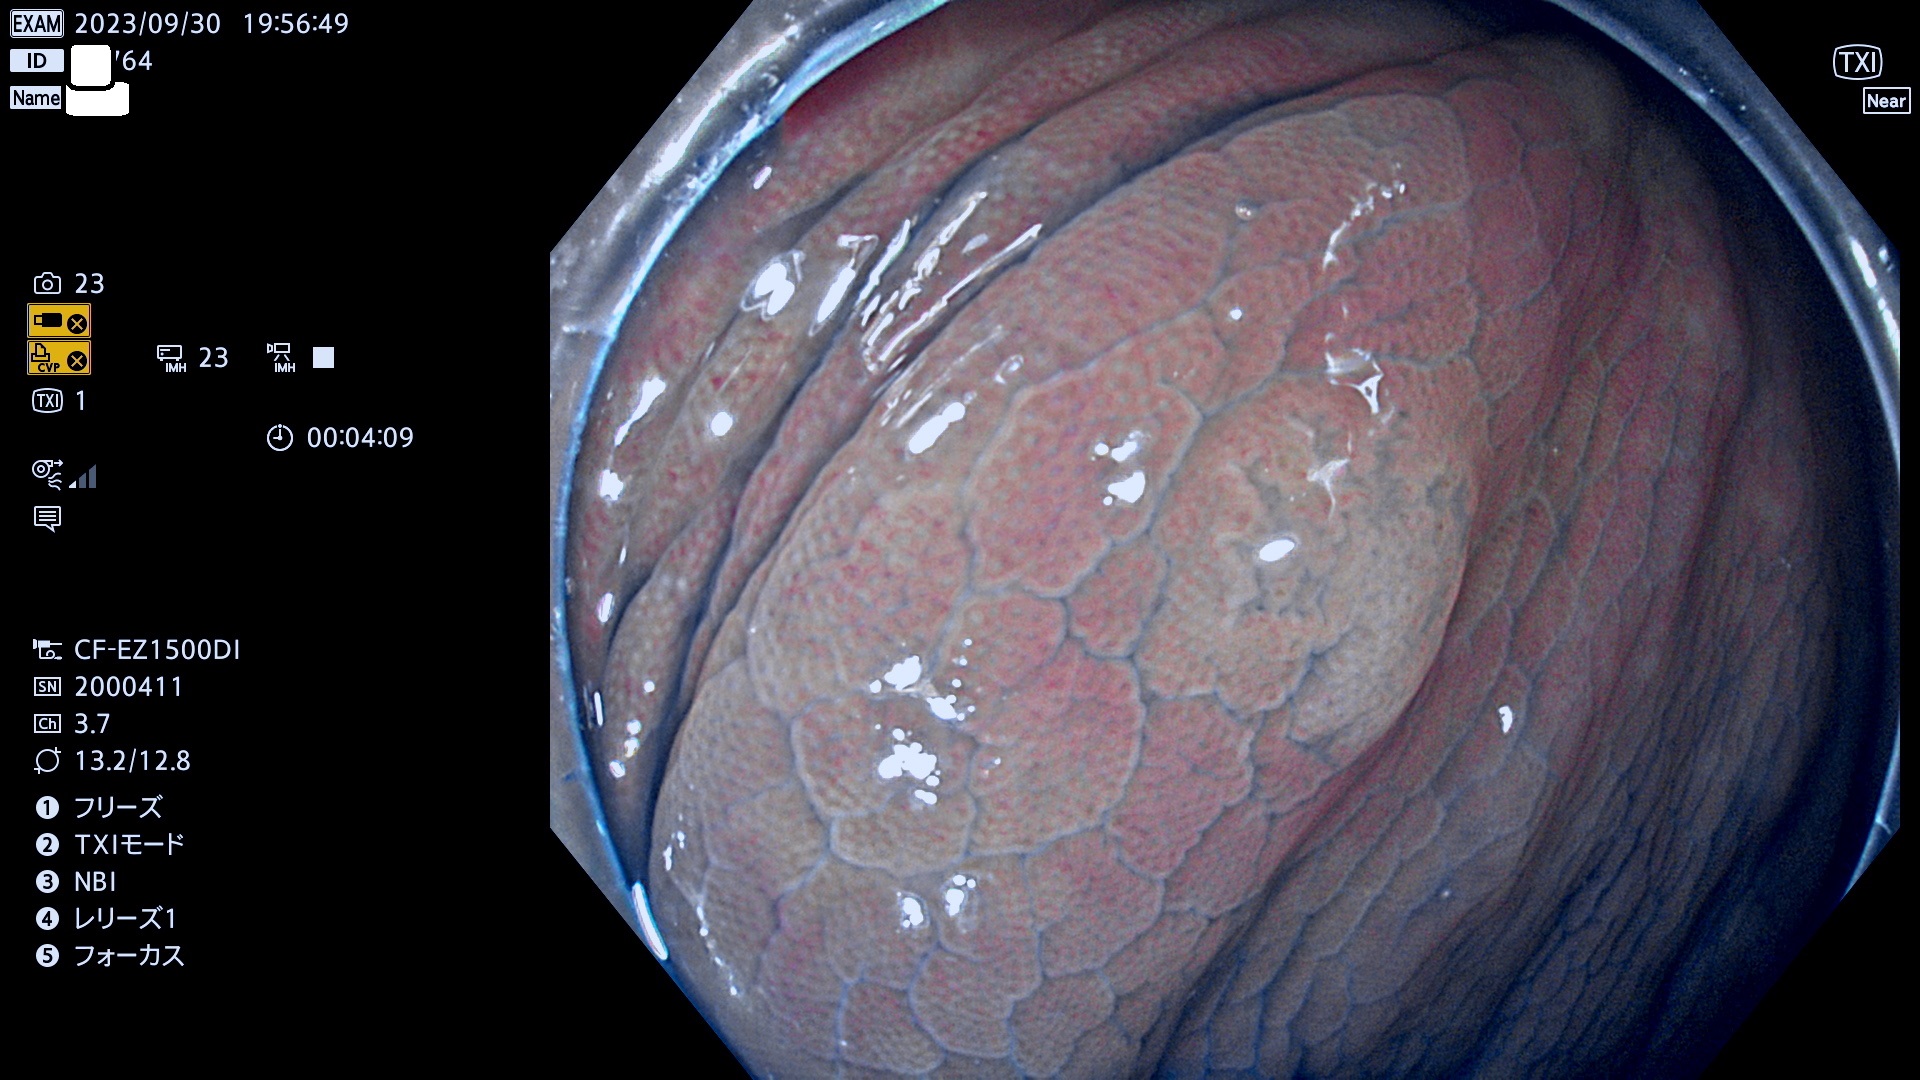

表面型腺腫(Flat Adenoma)の中で、完全に平坦な物をUb、陥凹している物をUcと呼びます。平坦隆起型(Ua)よりも、発見が難しく危険な病変です。このタイプは「内視鏡後・大腸癌の重要犯人」であり、この発見率は「腺腫発見率」よりも、重要な意味があります。

毎週の検査(木・金・土・日)に発見されたUb、Uc型・腺腫を、その週の日曜の夜にUPし1週間、提示します。

抽出の対象期間 2023年9月28日(木)〜10月1(日)の4日間(48件の検査)8件